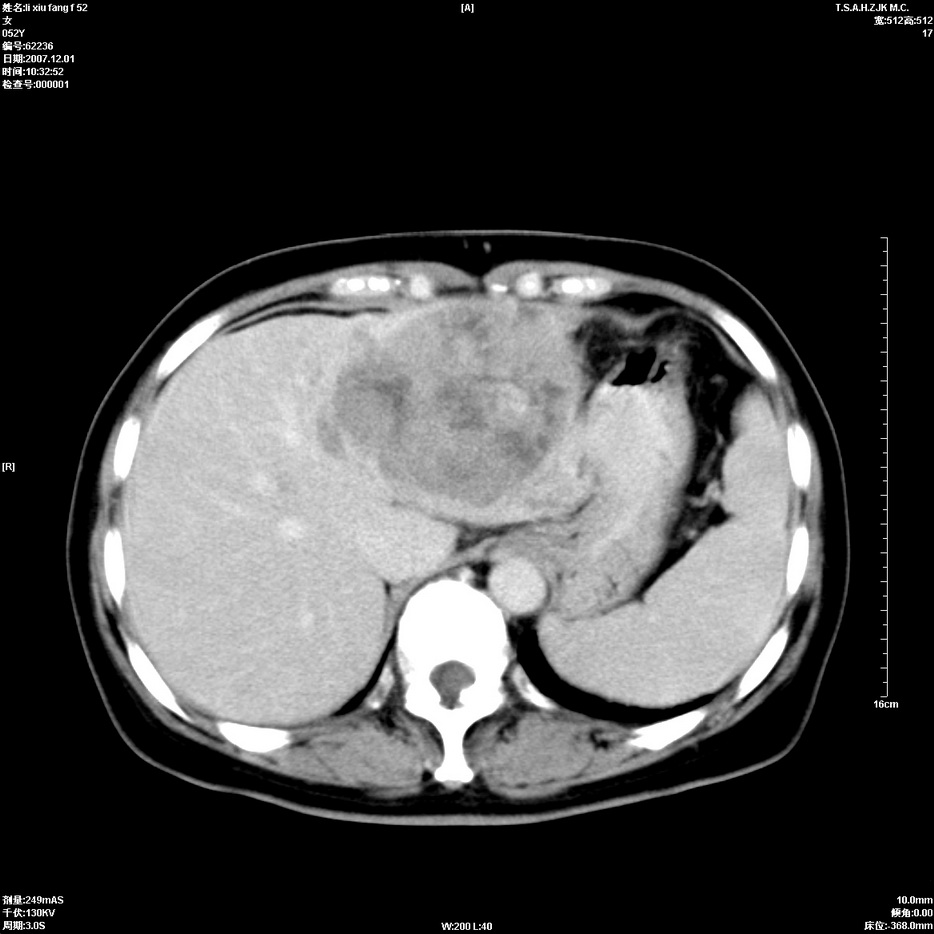

标题: CT12858:女,52岁,胎甲球蛋白861肝左叶占位,肝癌。下腔静 [打印本页]

标题: CT12858:女,52岁,胎甲球蛋白861肝左叶占位,肝癌。下腔静

肝左叶巨大低密度灶肿块,增强符合快进快出表现,有动静脉交通支;静脉期,下腔静脉内有充盈缺损,afp明显升高,支持肝癌并下腔静脉癌栓形成。

以下是引用拾荒者在2008-4-15 22:57:00的发言:[br]肝左叶巨大低密度灶肿块,增强符合快进快出表现,有动静脉交通支;静脉期,下腔静脉内有充盈缺损,afp明显升高,支持肝癌并下腔静脉癌栓形成。